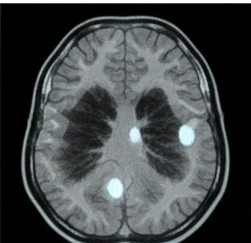

신경섬유종은 신경을 둘러싼 세포에서 발생하는 종양으로, 양성인 경우가 대부분이지만 생활의 질에 영향을 줄 수 있어 초기 신호를 인지하는 것이 중요합니다.

신경섬유종은 말초신경을 따라 발생하는 종양으로, 피부 아래 혹은 신경 내부에서 서서히 자라는 특징을 가지고 있습니다. 대부분 양성이지만 크기가 커질 경우 통증이나 기능 저하를 유발할 수 있습니다.

신경섬유종은 한 개만 발생하기도 하고, 여러 개가 동시에 나타나기도 하며, 발생 위치에 따라 증상 차이가 큽니다. 신경섬유종 초기증상을 이해하려면 먼저 이러한 기본적인 특성을 아는 것이 중요합니다.